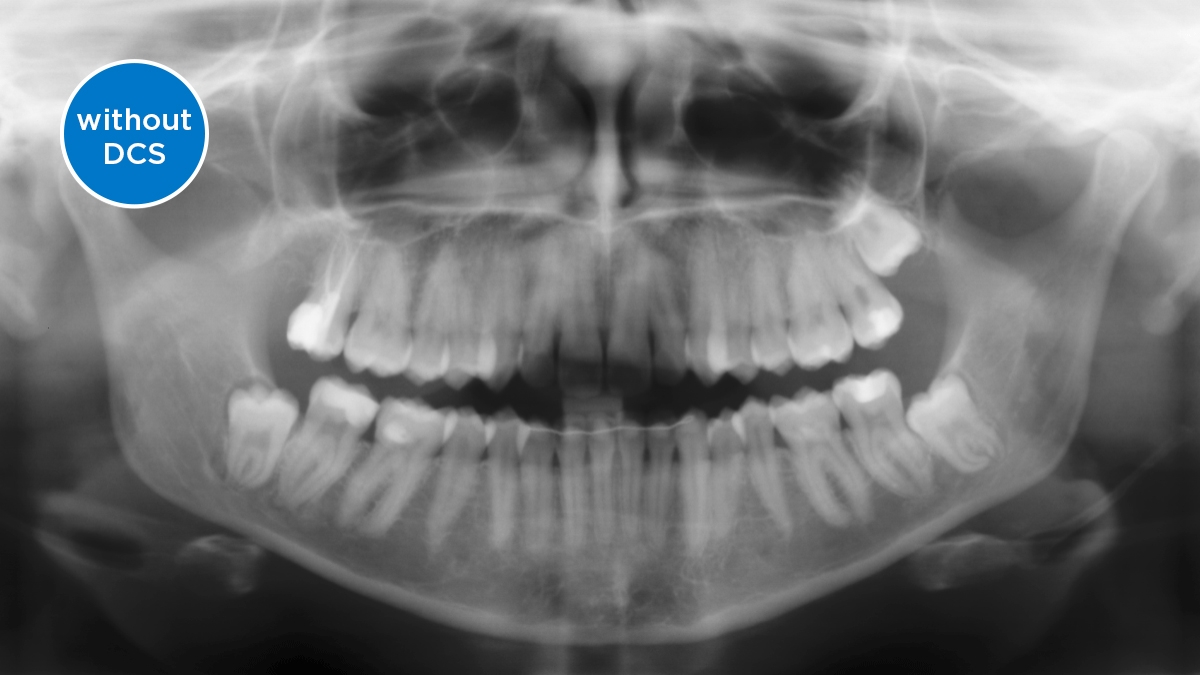

We developed a 10-point concept for easy patient positioning and X-ray imaging. Our concept is primarily about two things: high image quality and comfort for the patient and the assistant. This concept supports and provides the tools needed to ensure high-quality images for treatment analysis and focuses on ergonomics and comfort for the patient and assistant. The patented bite block technology, for example, automatically establishes the correct inclination of the patient's head, positioning the patient in the occlusal plane, partnering with the 3 point head fixation and firm handles to ensure stable positioning-limiting unnecessary correction scans.